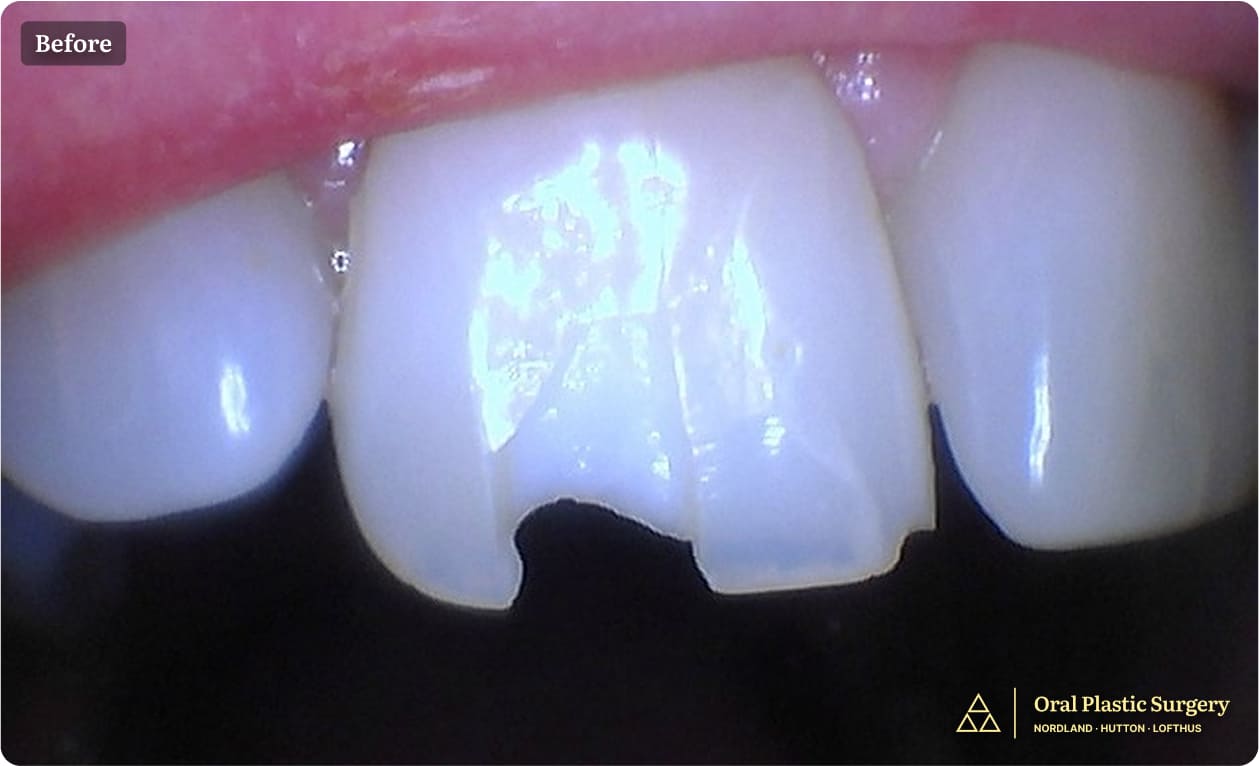

Seeking to improve her smile, Marianne had internal whitening performed by an endodontist. However, just three months after that procedure, the tooth’s crown fractured spontaneously.

Tooth #8 shows a visible fracture, indicating structural compromise and the need for further evaluation and treatment